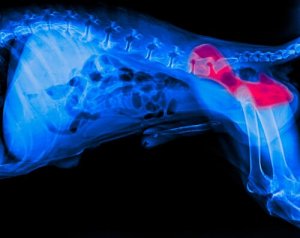

Dysplasia is a condition that affects the hip joints and the surrounding area. It is caused by a malformation of the femoral head and the corresponding hip joint. When this happens, the joint can start to deteriorate, causing discomfort and lameness.

Hip dysplasia has a number of symptoms. The most common include lameness, difficulty getting up or a dog continually staying on its feet. So, if you notice any of these symptoms, you need to consult a vet, who will do an x-ray to confirm the diagnosis.